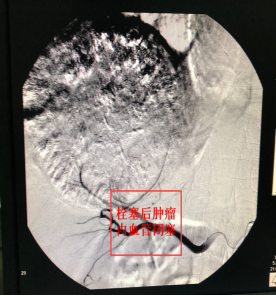

通过与患者家属充分沟通并征得同意后,肿瘤血液科于3月4日成功为患者实施TACE治疗。仅在大腿根部皮肤上穿刺3~5毫米的小口,经股动脉插管至肝癌供血动脉,采用局部靶向药物灌注及栓塞肿瘤供血血管的方式集中杀灭肿瘤细胞。

术后第2天,患者便能下床活动,于3月10日出院。1个月后,患者返院复查肿瘤缩小至8cm左右,肝静脉癌栓明显缩小,AFP由术前大于1000ng/ml降至正常范围,为下阶段根治性手术切除或放疗创造了条件。